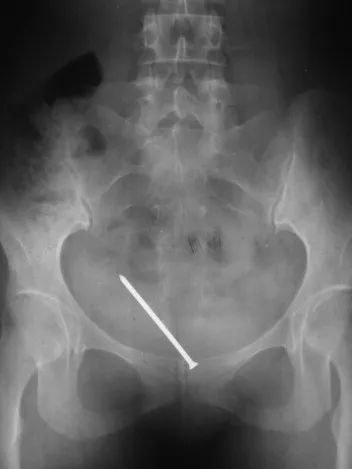

结果一看片子,瞬间来精神了:X线片清楚地显示,患者膀胱里横躺着一根温度计……

膀胱里的温度计丨医生供图这对夫妻盯着我:“大夫,您看怎么办?”

钉子丨参考文献8